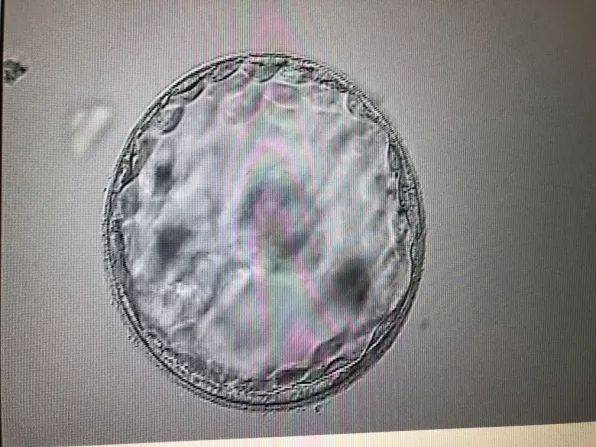

飞机在飞行过程中会受到来自地球表面和宇宙空间的辐射。虽然这种辐射的强度相对较低,但长期暴露可能对生殖系统产生不利影响。尤其是对于孕妇和准备怀孕的人群,辐射可能增加胎儿畸形和胚胎死亡的风险。